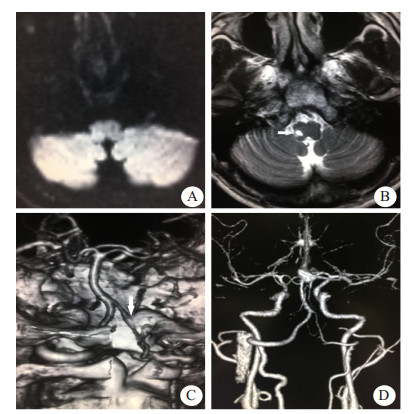

| A:首次头颅DWI检查结果阴性;B:48 h后复查头颅DWI可见左侧延髓背外侧高信号(箭头示);C:颈部血管ceMRA可见左侧椎动脉局部狭窄(箭头示);D、E:高分辨率磁共振可见血管壁间半月形高信号(箭头示) 图 2 例2患者影像学检查结果 |

患者2,男性,53岁,因“突发眩晕3 h”就诊急诊。患者3 h前突发出现眩晕,呈持续性,恶心呕吐,无耳鸣及听力减退,无口齿不清,无口角歪斜,无肢体瘫痪。既往体健,无烟酒史,否认遗传病及传染病,否认外伤及药物滥用。查体:意识清楚,口齿清,两侧瞳孔等大,对光反射存在,双侧眼球向右侧凝视可见水平眼震,向左侧凝视眼震幅度减弱,眼震方向不变,存在固视抑制,鼻唇沟对称,伸舌居中,颈软,心律齐,四肢肌张力正常,四肢肌力Ⅴ级,两侧指鼻试验、跟膝胫试验阴性,感觉检查正常,两侧病理征阴性,左侧甩头试验阳性。辅助检查:血常规、超敏CRP、肝肾功能、血糖、PT、INR、心肌酶谱均正常范围。头颅CT平扫未见明显异常。头颅DWI未见明显异常。急诊诊断前庭神经炎,予以异丙嗪针、甲泼尼龙针、泮托拉唑针治疗。48 h后收入病房,患者眩晕无好转,出现左侧颜面及右侧肢体麻木症状,复查头颅DWI提示延髓梗死,予以阿司匹林、氯吡格雷、阿托伐他汀治疗。进一步完善颈部血管ceMRA可见左侧椎动脉V4段局部狭窄,高分辨磁共振检查可见管壁间亚急性血肿。最终诊断Wallenberg综合征、VAD,经治疗后患者症状好转,出院后服用阿司匹林、阿托伐他汀。门诊随访1年无再发,建议完善脑血管造影检查,患者拒绝。本病例资料的报道已获得患者知情同意。

例2患者无明显脑血管病危险因素,表现为眩晕,无局灶性神经功能缺损,查体可见周围性眼球震颤,床旁头脉冲试验(HIT)左侧阳性,头颅DWI阴性,诊断前庭神经炎,予以甲泼尼龙针抗炎治疗。发病48 h后患者出现感觉障碍,复查头颅DWI可见延髓梗死病灶,改用阿司匹林、氯吡格雷、阿托伐他汀,进一步完善血管检查发现左侧VAD,为病灶责任血管。研究表明,有35%的临床表现类似前庭神经炎的脑卒中患者在急诊被误诊,其中40%的患者病情会进展[10]。Kim等[11]研究认为,局限于前庭神经核或延髓背外侧的小面积梗死可以表现为孤立性眩晕,缺乏异常神经系统症状体征,早期的磁共振检查可呈阴性,患者头脉冲试验阳性,临床表现类似前庭神经炎,容易误诊。该患者早期临床表现类似于前庭神经炎,考虑与病灶局限于前庭神经核及延髓背外侧较小区域有关,直到症状进展出现交叉性感觉障碍,复查头颅DWI,最终确诊。